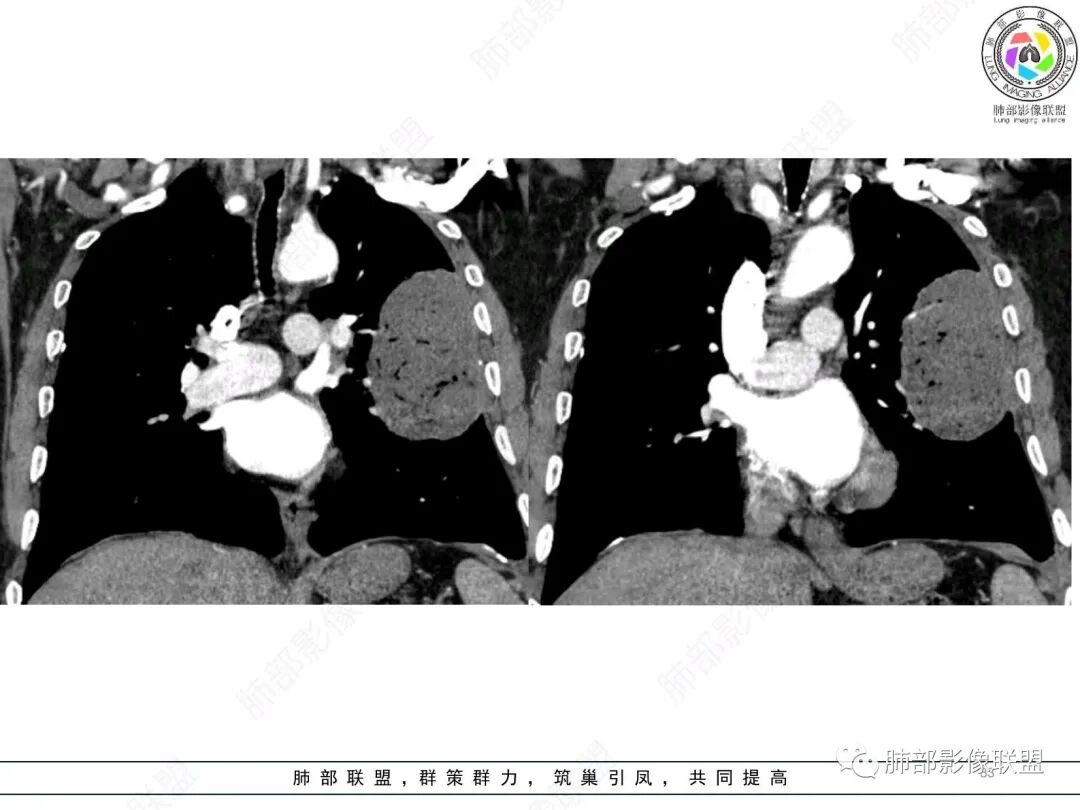

左肺上叶大肿块,膨胀性生长,边界清,密度较低,见部分坏死区,强化弱,肿块见支气管充气V扩张征,分布僵直,枯树枝特点,另一个重要特点血管造影征,淋巴瘤,肿块长轴与胸膜平行,与隐球菌鉴别,隐球荚膜抗原检查,明确诊断经皮肺穿刺。另胸膜钙化(问诊既往有无患胸膜炎病史)。

左肺上叶胸膜下肿块,宽基底与胸膜相连,跨叶裂,边缘清晰膨隆,其内支气管充气,部分扩张、僵直,无明显强化,血管造影征,考虑淋巴瘤,鉴别腺癌

左肺胸膜下巨大占位,跨叶裂,宽基底与胸膜相连,胸膜钙化,平扫密度较低,强化不明显,可见内部血管显影,支气管充气征和扩张,考虑为恶性,倾向于淋巴瘤

左侧胸腔巨大肿块,跨叶生长,临近胸膜钙化,边缘模糊,可见支气管影,定位肺内,增强后轻度强化,边缘见血管影,考虑淋巴瘤,鉴别肉瘤

支持淋巴瘤,左上肺大肿块,有分叶,边缘光整,病灶内密度不均,可见支气管扩张征,增强后可见血管影征。周围肺野清晰。

左肺上叶肿块,宽基底与胸膜相连,跨叶裂,边缘清晰膨隆,可见小分叶,其内支气管充气,部分扩张、僵直,呈枯枝征,支气管达边征,增强无明显强化,可见血管造影征,考虑恶性病变,淋巴瘤,鉴别粘液腺癌。

大肿块,边缘光滑,深分叶

近端支气管堵塞、推移为主

部分类似于脐凹征

内部支气管扩张

肺动脉推移为主,边缘部分进入